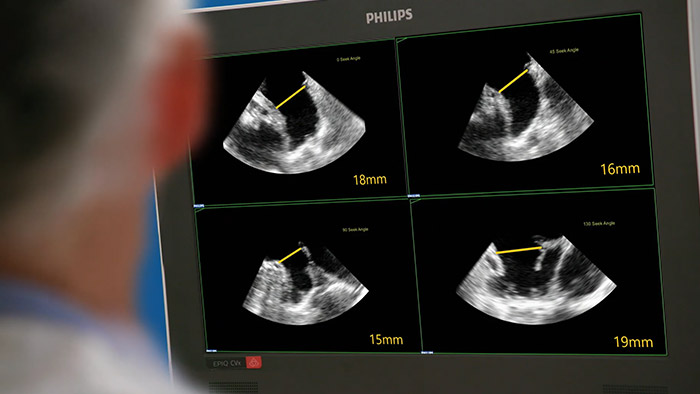

Sistema de ecografía intervencionista EPIQ CVxi

Evaluar la orejuela izquierda de forma rápida, fácil e intuitiva. La solución para la LAA de Philips en EPIQ CVxi.